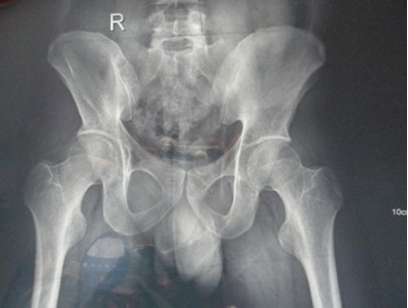

(图:许先生入院做拍摄的CT图)

X线片示:右侧骶髂关节面毛糙、模糊,关节面下见数个类圆形、半月形囊样低密度区,边界清晰、可见硬化,右侧骶髂关节间隙不窄,左侧骶髂关节骨质完整,未见骨质破坏或吸收,关节面光滑,关节间隙无增宽或狭窄,关节腔无积液,未见异常软组织肿块影。诊断:右侧骶髂关节改变,考虑强直性脊柱炎。